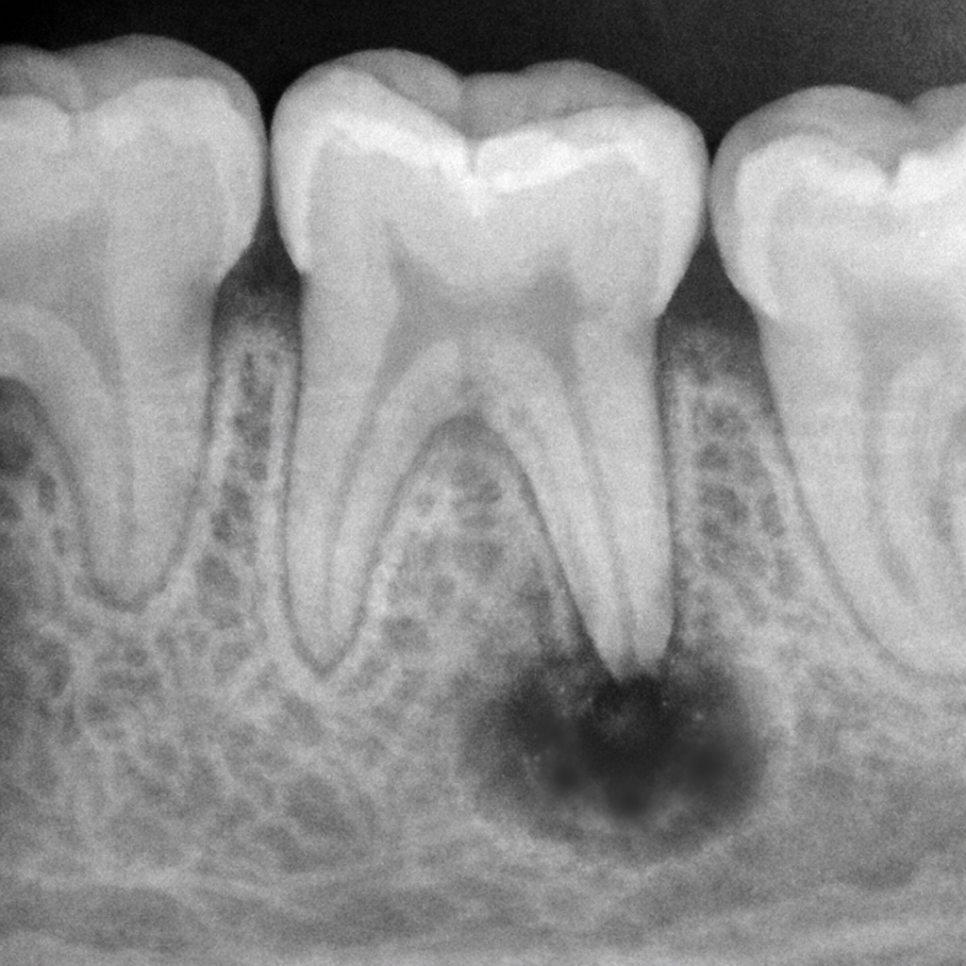

특히 충치가

신경(치수)에까지 도달하면,

통증과 감염을 유발할 수 있어

충치는 초기에는 치아 표면에만 머물지만,

점차 깊어져 치수까지 도달할 수 있습니다.

이 과정에서 염증과 감염이 시작됩니다.

그대로 방치하게 되면

뿌리 끝에 농양이 형성되고,

심한 경우에는 아래쪽 영구치

씨앗(치배)에까지 영향을 주어

*유치가 빠진 후 그 자리에서 자라날 영구치의 초기 발달 단계

법랑질 저형성증(Enamel Hypoplasia)

영구치 변색이나 형성 이상이 생기기도 합니다.